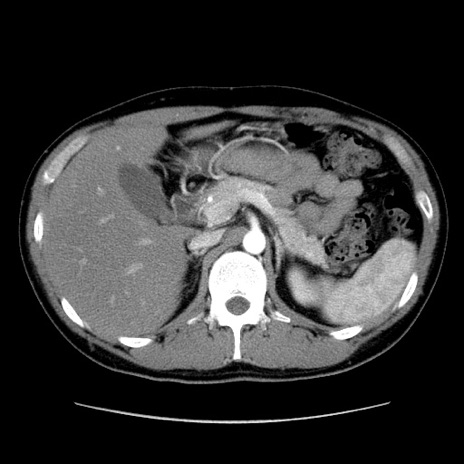

冠状断像

【症例】20歳代 男性

【主訴】心窩部痛

【現病歴】今朝より上腹部痛あり。一旦軽快していたが再度出現したため救急要請。昨日夕に白身の魚を含む刺身を食べた。

【身体所見】BP 136/89mmHg、HR 74/min、BT 37.0℃、腹部:膨満、軟、心窩部に圧痛あり。反跳痛なし、筋性防御なし、腸雑音やや亢進あり。

【データ】WBC 17700、CRP 0.48